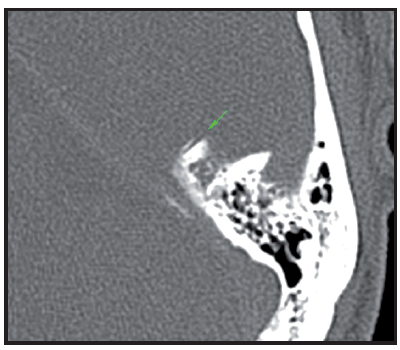

Figure 4a Reconstrucciónn MPR oblique parallel to the plane of the tympanic tegmen. Level window 600 and window width UH 2500 UH. The green arrow indicates the CSCS lacking its superior bony wall.

Figure 4b Rendering reconstruction volume highlighting the defect adjacent to the upper wall of CSCS, shown by arrows 4c rojas. Figure bone surface. MPR oblique parallel to the plane of the CSCS which highlights the ósea.VCL wall dehiscence. With the clinical suspicion of DCSS syndrome in left ear temporal bone CT is performed, with cuts of 0.5 mm, which confirms the clinical diagnosis.